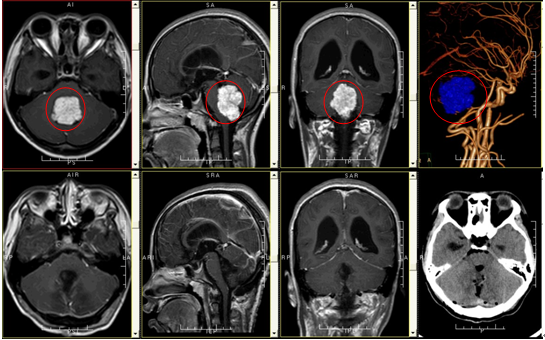

刘某某,女性,15岁, 因反复出现视物模糊10天入院。入院时双眼视物模糊,双眼视力低于4.0,眼前15cm可看清文字,视野粗测正常,双眼外展时左右震颤,上视时无震颤,头颅CT示:第四脑室占位性病变,伴梗阻性脑积水。

诊断:1、第四脑室肿瘤,2、梗阻性脑积水

治疗:全麻下行四脑室肿瘤切除术,术程顺利,术后予预防感染、改善脑功能、改善微循环、对症、支持等综合治疗。术后病理结果示:脉络丛乳头状瘤,术后复查头颅MRI增强扫描示:四脑室肿瘤切除术后改变,肿瘤已完全切除。